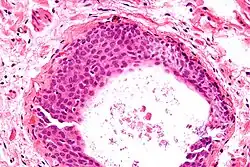

Additional images

High magnification micrograph of a Brenner tumor showing the characteristic coffee bean nuclei which are also seen in Walthard cell rests. H&E stain.

High magnification micrograph of a Brenner tumor showing the characteristic coffee bean nuclei which are also seen in Walthard cell rests. H&E stain.